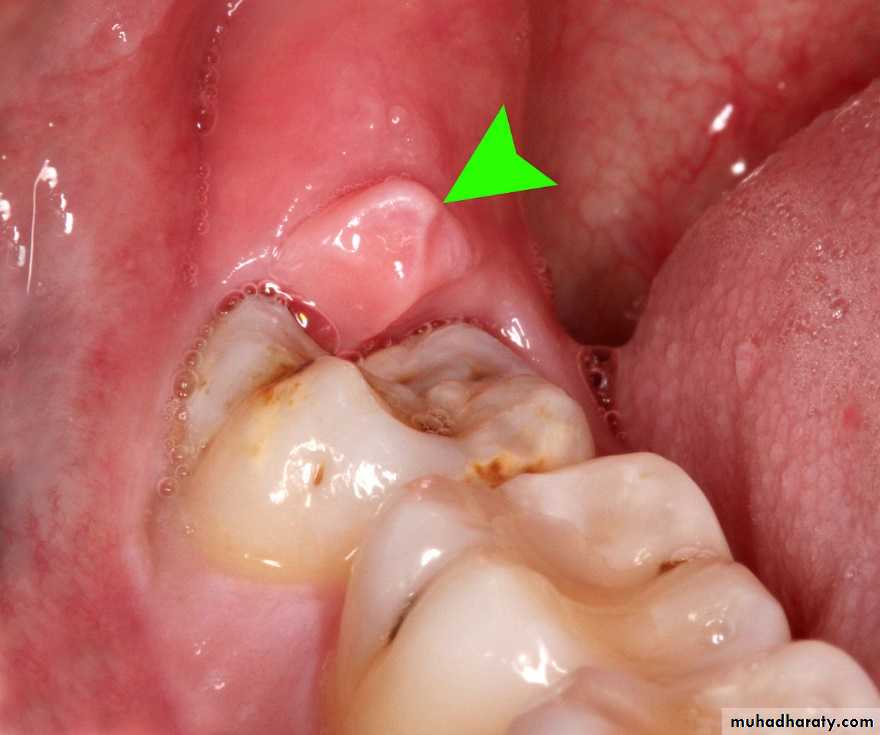

Pericoronal infections

Also called pericoronitis is an infection of the soft tissue covering the crown of a partially erupted tooth, it is almost always associated with partially erupted impacted lower third molars.Etiology involves:

• Food impaction between the crown and the overlying gum (operculum) which is a favorable site for bacterial proliferation and inflammation.

• Trauma to the overlying gum from the opposing tooth, but it is hard to determine whether the trauma occurs before or after the inflammatory edema of the gum.

• Virulent microorganism.

• Lowering of the host resistance.

Pericoronitis appears to be the result of a combination of the four mentioned etiological factors.

• The clinical presentation depends on the severity of infection:

Chronic pericoronitis is either asymptomatic or there is mild discomfort.

In Subacute pericoronitis there is a dull pain which is well localized, the gum pad may be tender and red and there may be expression of a white material from underneath the gum flap, this material is composed of desquamated epithelial cells, food stuff, dead and living bacteria, there may be slight trismus and lymphadenopathy (LAP).In Acute pericoronitis there is severe pain and limitation of mouth opening, intraoral swelling and there may be extr-aoral swelling as

well as fever, malaise and LAP. Pus may be expressed from underneath the flap, sometimes the pus may track submucosally and is expressed from a sinus in the molar or premolar region, this is termed migratory abscess.